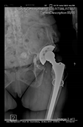

The guiding wire was inserted and controlled with fluoroscopy flashes (Figure 4). The drilling and reaming were carried out in accordance with the recommendations:

Figure 4.

The biocompatible aiming device after insertion of the guiding wire.

In all the cases operated with the above-described targeting procedure, the stems of the cups remained between the cortical bone surfaces without perforation of the linea terminalis, as shown by postoperative radiographs. There were no complicated surgical situations. In 16 cases, the wound healings were uneventful, and the hips were able to bear weight again after postoperative rehabilitation.